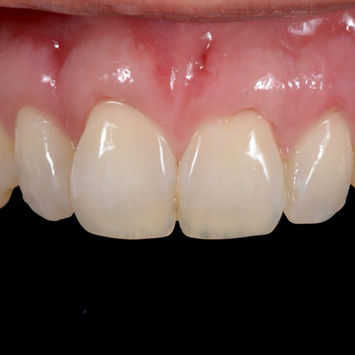

Avant / Après – Traitement des récessions gingivales et recouvrement radiculaire au maxillaire à Embrun

Patiente de 42 ans, habitante de Gap, est venue consulter le Cabinet Dentaire ASV à Embrun pour des récessions gingivales importantes au maxillaire. En plus d'affecter l'esthétique du sourire l'exposition des racines entraine une hypersensibilité dentaire.

- Recouvrement radiculaire pour protéger les racines exposées

- Renforcement du parodonte par greffe gingivale pour stabiliser les gencives

Résultat : Une esthétique dentaire et un confort retrouvés